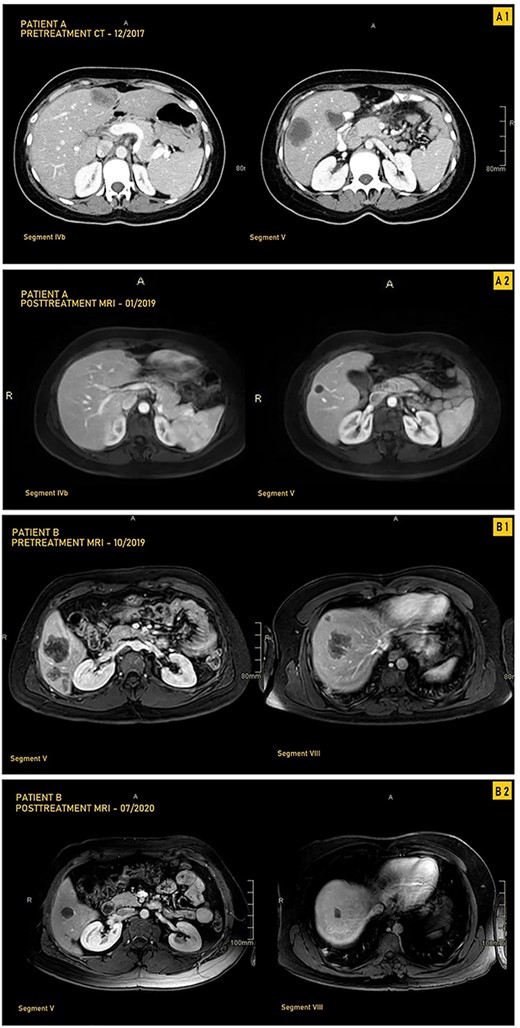

A 33-year-old female patient was diagnosed with a moderately differentiated invasive adenocarcinoma of the transverse colon with multiple bilobar liver lesions (Fig. 1A1 and Table 1). She underwent a laparoscopic subtotal colectomy, and the immunohistochemical analysis showed loss of MLH1 and PMS2 expression in tumor cells with retained MSH2 and MSH6, thus MMR-deficient (dMMR). She was started on FOLFOX (Oxaliplatin with 5-Fluorouracyl and Leucovorin) regimen with Avastin (Bevacizumab). Computed tomography (CT) scan was performed after her fourth cycle of chemotherapy and revealed an increase in size of the liver lesions (Table 1). She was started on pembrolizumab (19 cycles), and upon follow-up CT scans done every 3 months, there was a significant decrease in the size of the hepatic lesions (Fig. 1A2). She was reassessed and underwent liver resections of all her lesions. Final pathology was negative for residual carcinoma, with areas of necrosis and negative margins on surgical pathology.

CT and MRI images our two patients before and after treatment with pembrolizumab; (A1) Pretreatment MRI of our first patient in September 2017 showing most prominent lesions, located in Segments IVb and V, on axial enhanced CT after contrast administration; (A2) Posttreatment axial enhanced T1-weighted MRI of our first patient in January 2019 showing most prominent lesions located in Segments IVb and V; the lesion in Segment V is smaller, measuring 1.4 cm, and is completely necrotic; (B1) Pretreatment axial enhanced T1-weighted sequence MRI performed on 3Tesla field strength following gadolinium contrast administration in our first patient in October 2019 showing most prominent lesions, located in Segments V and VIII; the largest metastatic lesion is a 4.8-cm heterogeneously enhancing metastatic lesion in Segment VIII; (B2) Posttreatment axial enhanced T1-weighted sequence MRI performed on 3Tesla field strength following gadolinium contrast administration in the hepatobiliary phase in our second patient in July 2020, showing most prominent lesions located in Segments V and VIII; the largest lesion in Segment VIII decreases in size to 1.5 cm following treatment and is completely necrotic.

A 33-year-old male patient was diagnosed with adenocarcinoma of the transverse colon with 24 bilobar hepatic metastases. He was started on four cycles of Xelox and Avastin after which some lesions responded to treatment while others did not, as evidenced by changes in the hepatic lesions on magnetic resonance imaging (MRI) (Fig. 1B1 and Table 1). Immunohistochemical analysis showed loss of MLH1 and PMS2 with retention of MSH2 AND MSH6; he was started on pembrolizumab (12 cycles) with consistent interval decrease in size of both the colonic mass and hepatic lesions over several follow-ups every 3 months (Table 1). After multiple months, MRI showed a marked decrease in the transverse colonic mass and all hepatic lesions which became necrotic; four hepatic lesions became barely visible or disappeared (Table 1 and Fig. 1B2). He underwent a transverse colectomy with primary anastomosis and metastasectomy where all hepatic lesions were negative for residual carcinoma with negative surgical margins and areas of necrosis.